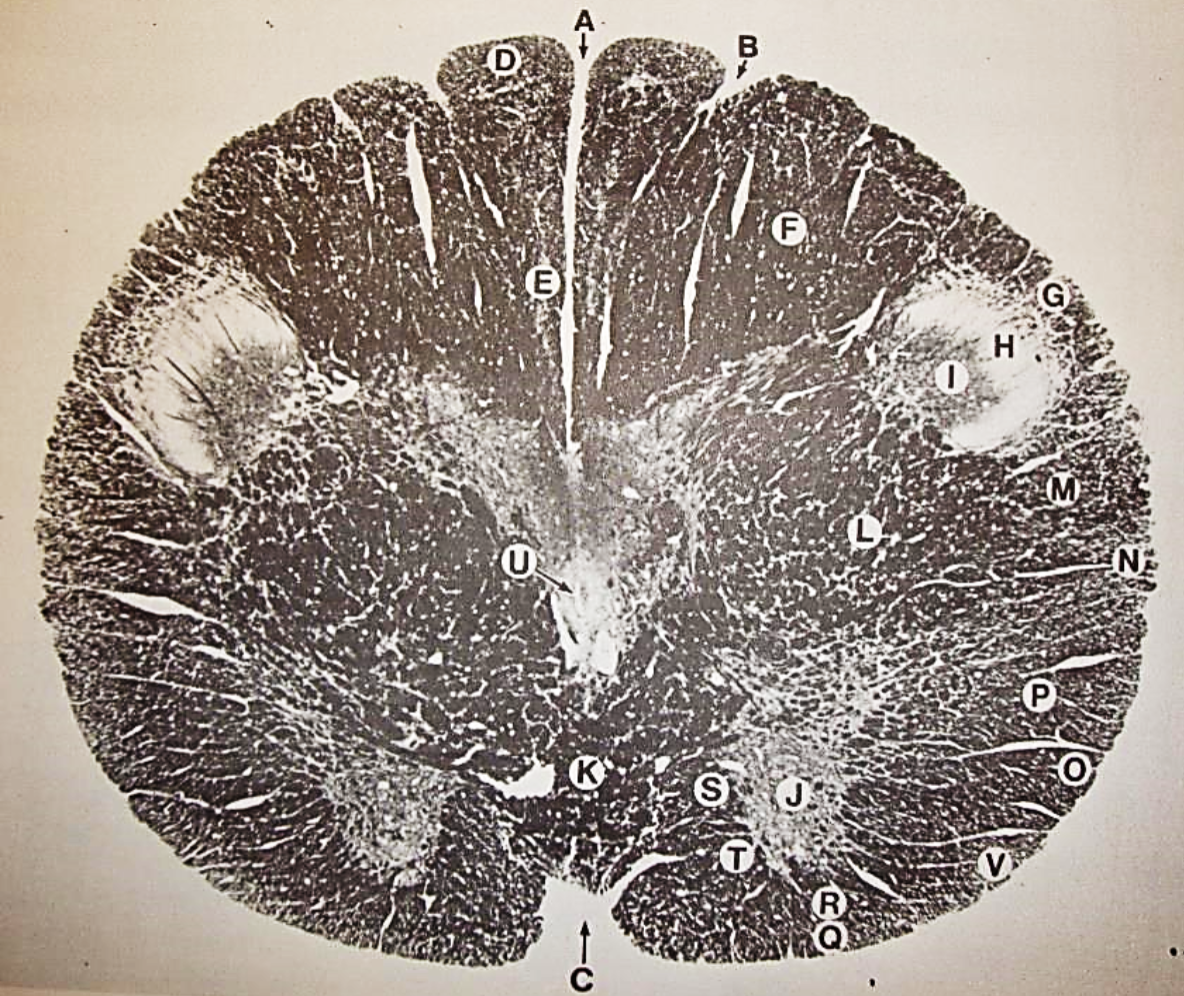

A

posterior median sulcus

B

posterior intermediate sulcus

C

anterior median fissure

D

gracile fasciculus

E

Gracile nucleus

F

fasciculus cuneatus

G

spinal trigeminal tract

H+I collectively

spinal trigeminal nucleus

J

Accessory nucleus

K

pyramidal decussation

L

lateral corticospinal tract

M

rubrospinal tract

N

posterior spinocerebellar tract

O

anterior spinocerebellar tract

P

lateral spinothalamic tract

Q

anterior spinothalamic tract

R

lateral vestibulospinal tract

S

medial longitudinal fasciculus

T

tectospinal tract

U

central canal